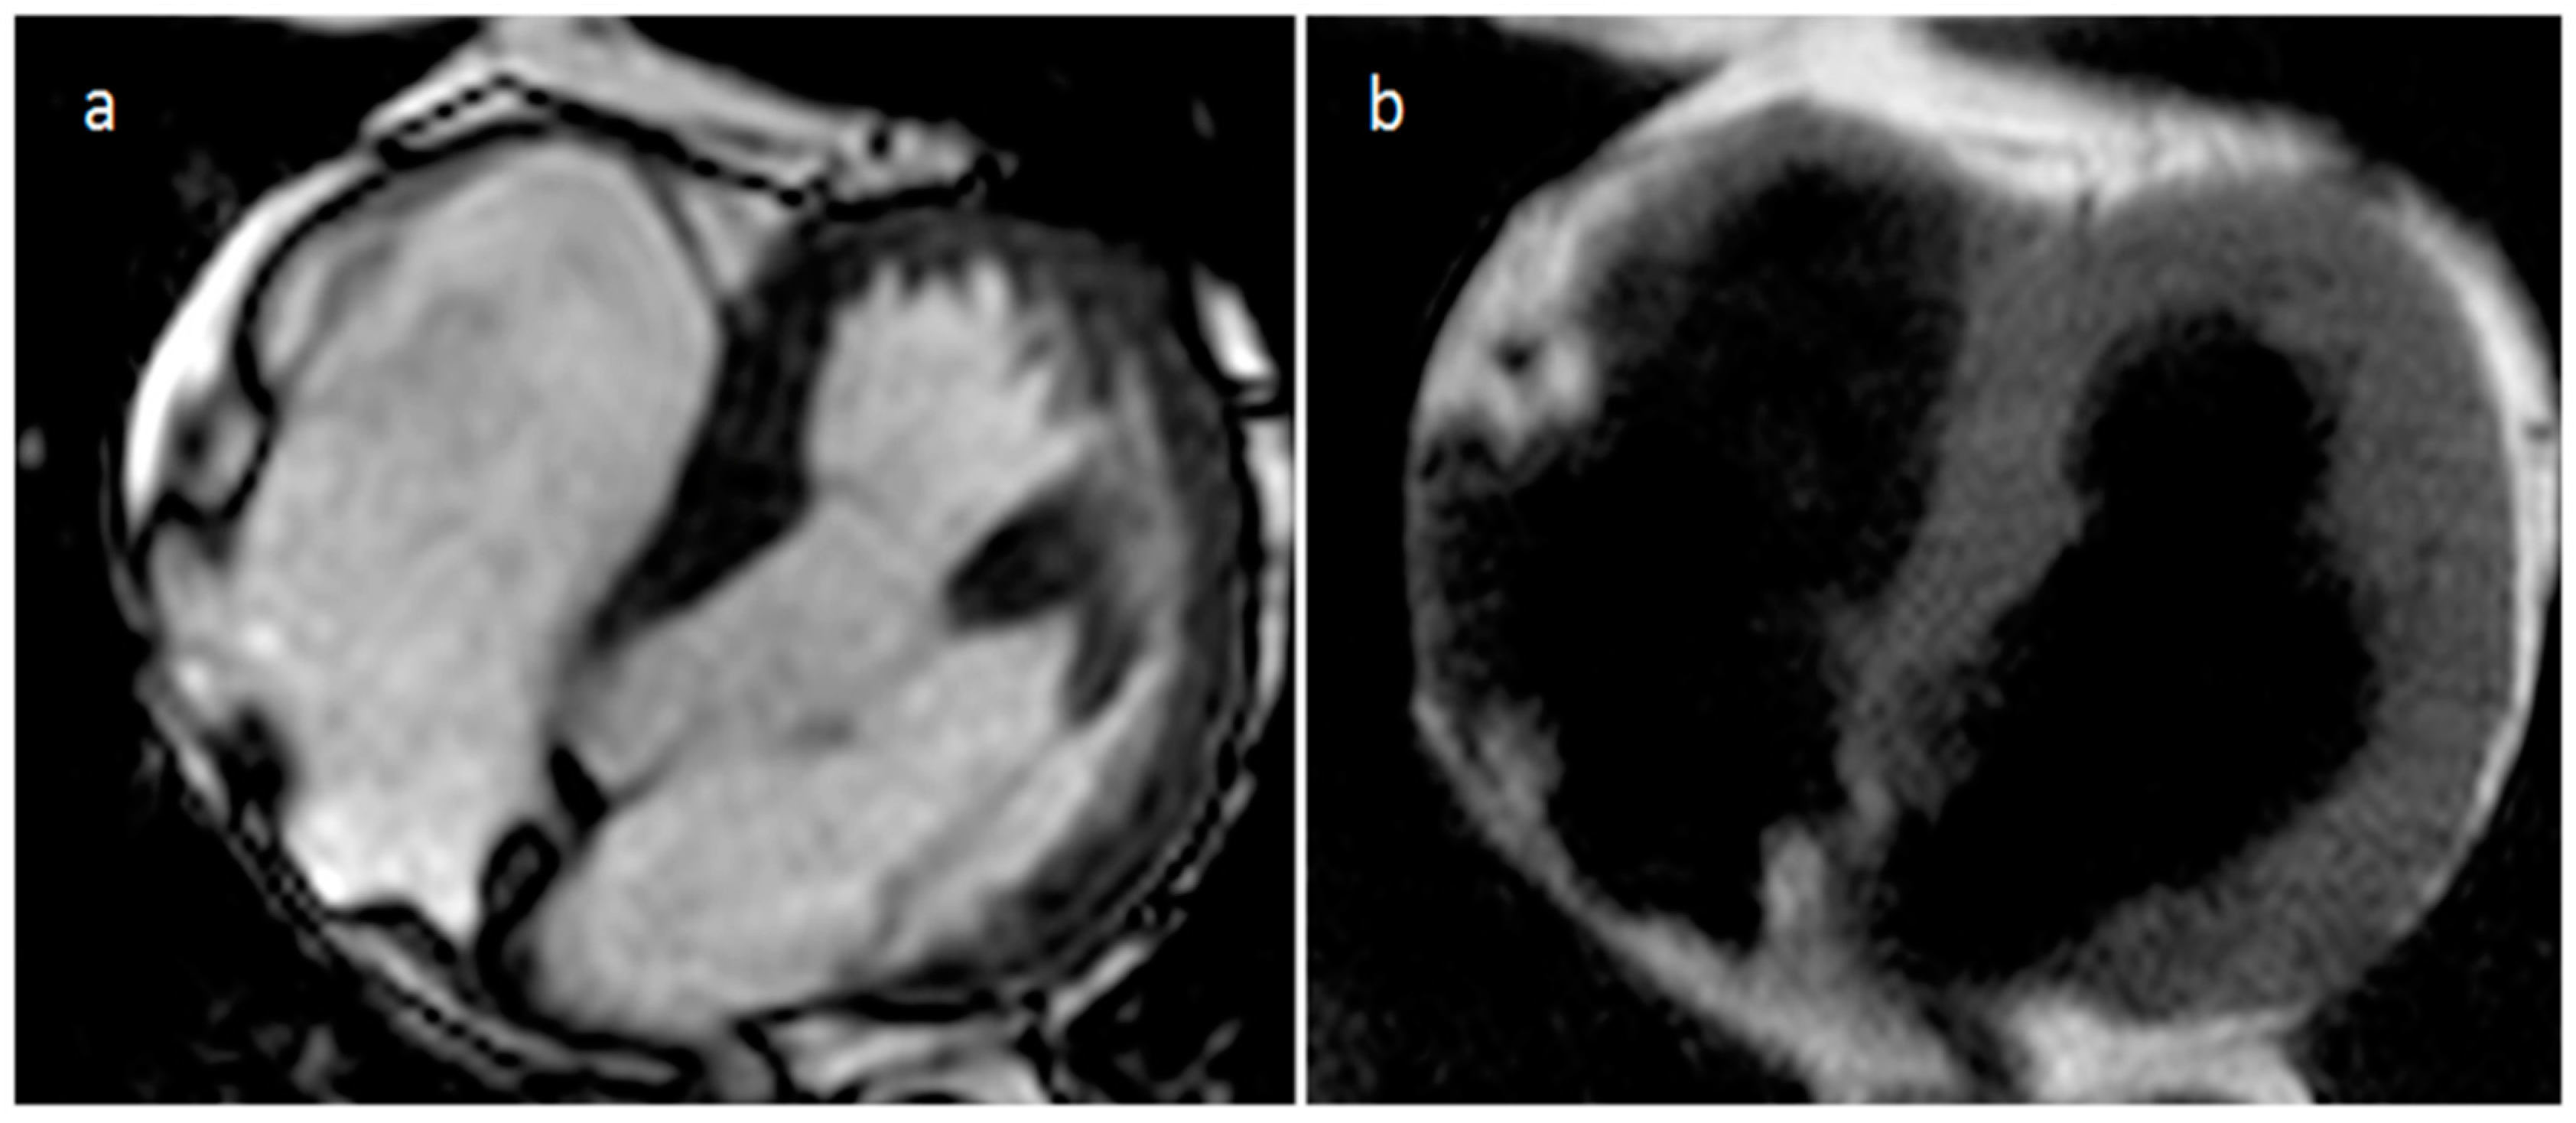

3.1. Thrombus

| Thrombus | Adulthood | LA, LAA (AF) LV (MI) | Asymptomatic, embolic events | Non-enhancing Intracardiac lesion | Acute: Low echodensity, rounded with smooth contours Chronic: High echodensity, linear or crescentic lesions along the endocardial surface | Low attenuation, no contrast enhancement, chronic thrombus may be calcified Usefulness of delayed CT imaging, as in the LAA stasis of blood can simulate a thrombus on early arterial images | Acute: hyper T1w and T2w Subacute: hyper T1w and hypo T2w Chronic: low T1w and T2w No enhancement. |